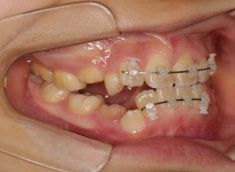

治療開始時

治療開始から11ヶ月